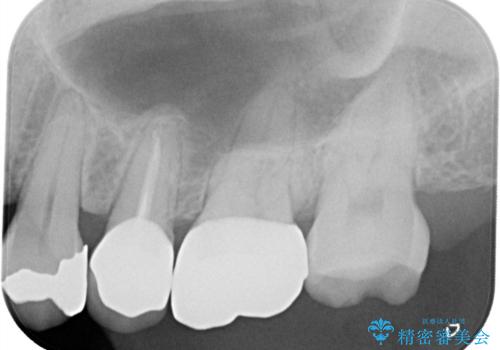

- 「何もしなくても歯が痛む、咬むと歯が痛む」を主訴に来院された患者さんです。検査の結果、歯髄の部分壊死と診断しました。根管治療を行いファイバーコアとオールセラミッククラウンで治療を行いました。

- 297,000円【根管治療110,000円+ファイバーコア22,000円+仮歯11,000円+オールセラミッククラウンスペシャル154,000円】費用は治療当時の料金となります